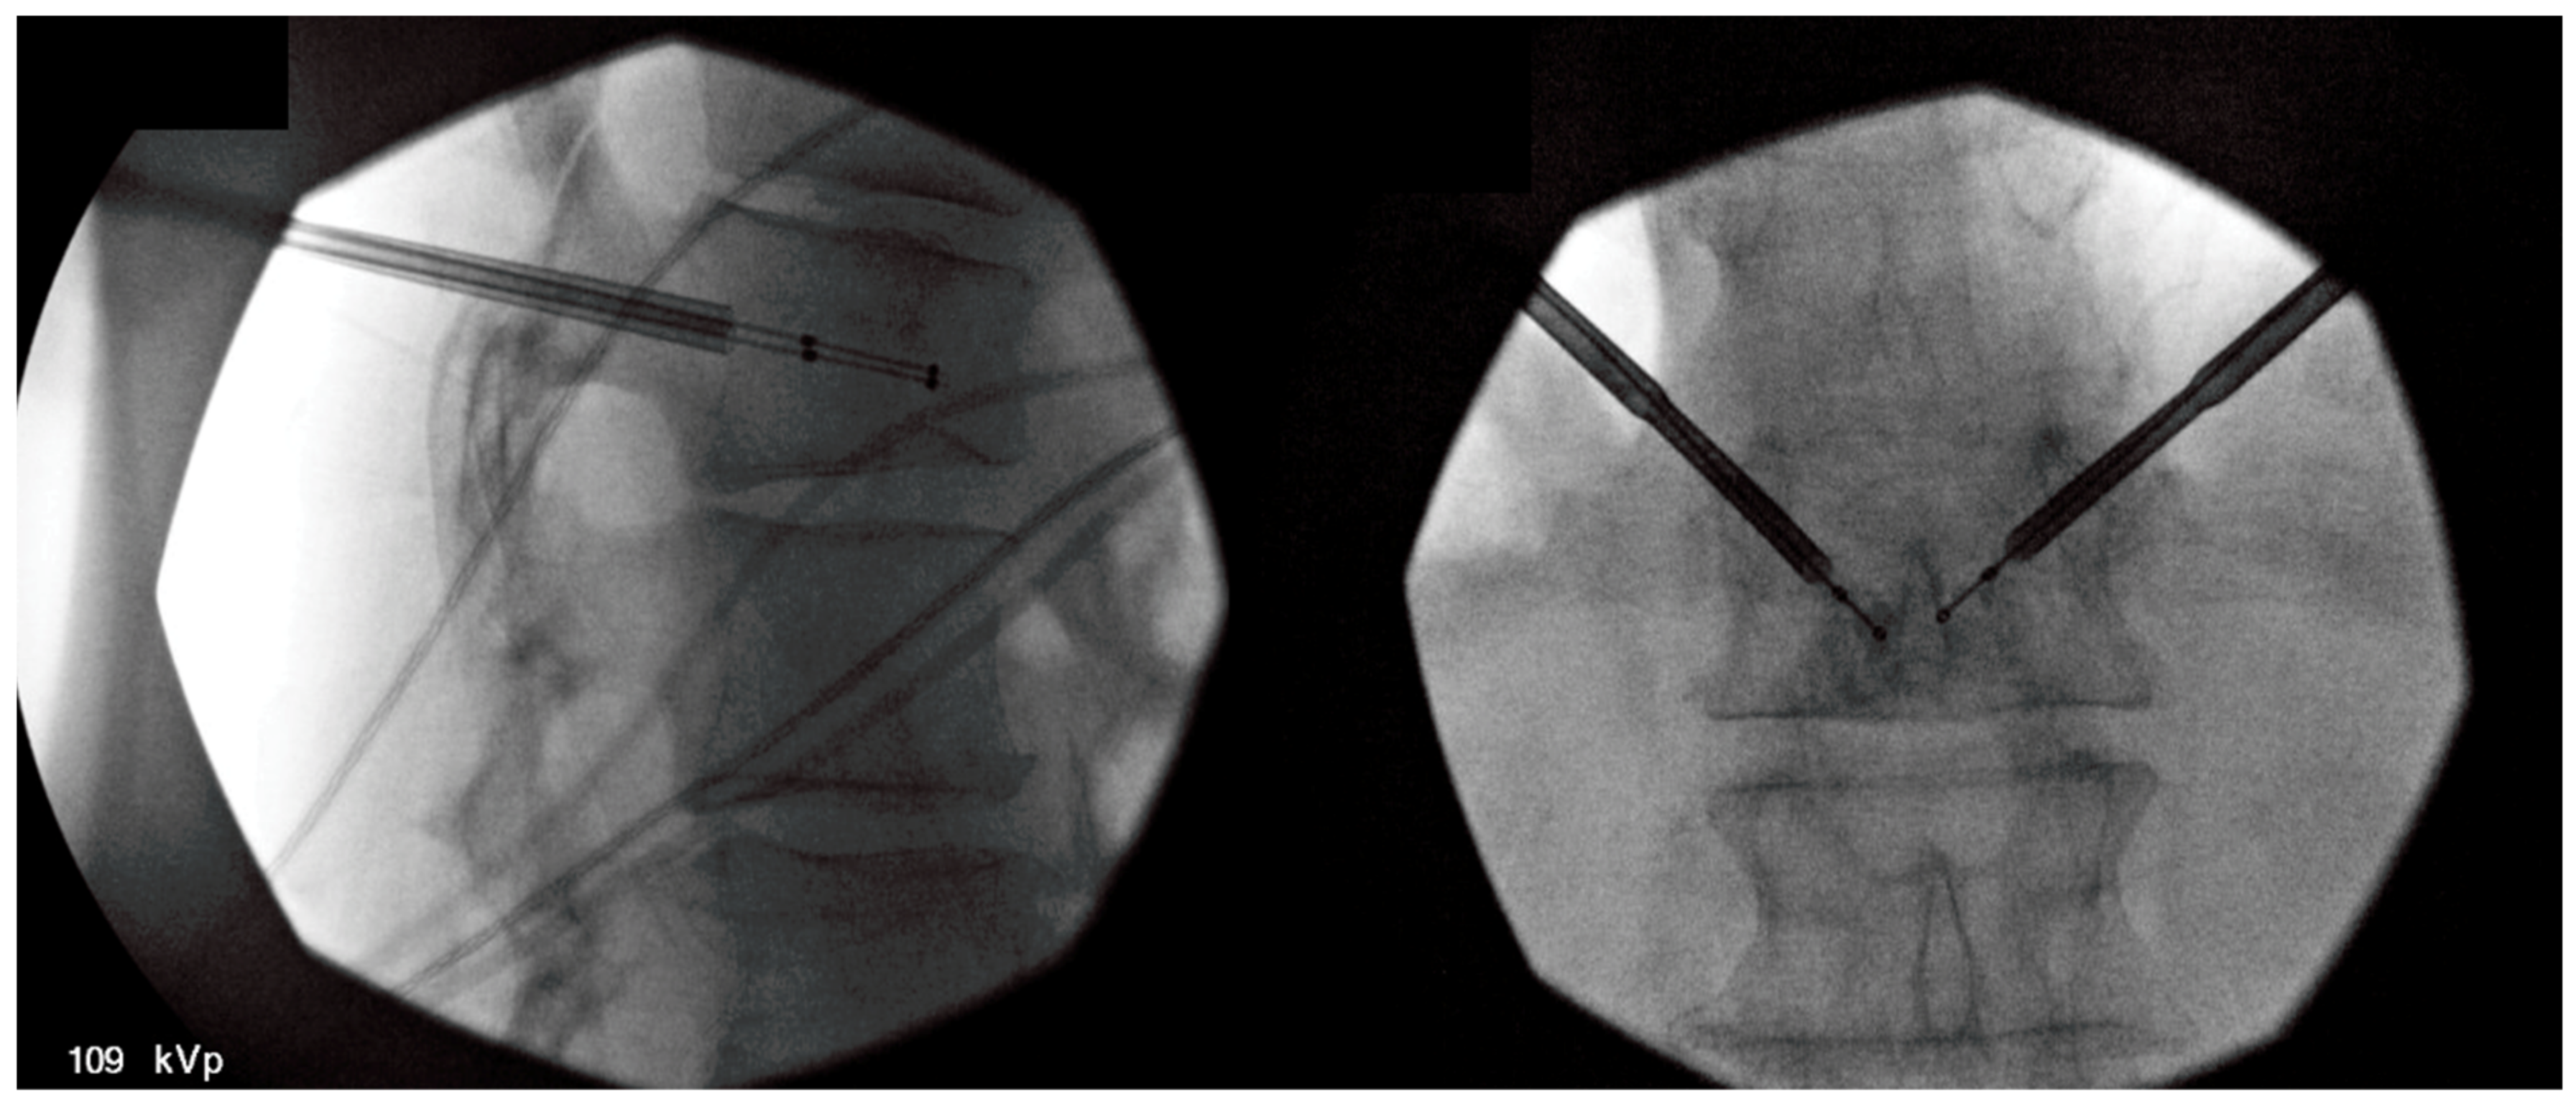

Spinal tumor ablation (STA) is an innovative, minimally invasive option to address pain from vertebral body tumors. Percutaneous treatment of non-spinal bone tumors was described first in 1992 with subsequent analysis of radiofrequency ablation (RFA) in a variety of non-spinal osseous structures [70,71]. The feasibility of STA was introduced in 2000 by Dupuy and colleagues with two human cases following an investigation on porcine models [72]. STA utilizes a percutaneous approach whereby one or more electrodes are inserted into an affected vertebra, and high-frequency alternating current ablates the tumor site. (Figure 3). Conventional radiofrequency causes coagulative necrosis with tissue temperatures of 50–100 °C [12,73,74,75]. Cryoablation applies a reverse technique for cell lysis with tissue temperatures reduced to −40 °C [76]. Subsequent pain relief is thought to derive from the destruction of periosteal nociceptors neural tissues involved in pain transmission. Either approach uses only a single outpatient treatment with mild to moderate sedation and local anesthetic. Several companies have created systems with radiofrequency, microwave, or cryoablation approaches. [13,72,74]. Treatment goals of STA may be a reduction in large tumor burden or as a definitive treatment for benign small tumors, such as osteoid osteomas or osteoblastomas [74]. Patient selection should include a comprehensive, interdisciplinary assessment of patient risk factors, medical comorbidities, and tumor burden. Generally accepted contraindications are active infection, coagulopathy, and contraindications to anesthesia or analgesia [77].

Figure 3.

Fluoroscopic-guided vertebral body tumor ablation. The picture on the left shows a lateral view of bipedicular approach access, while the picture on the right shows an anterior–posterior (AP) view of the procedure with midline probe placement.